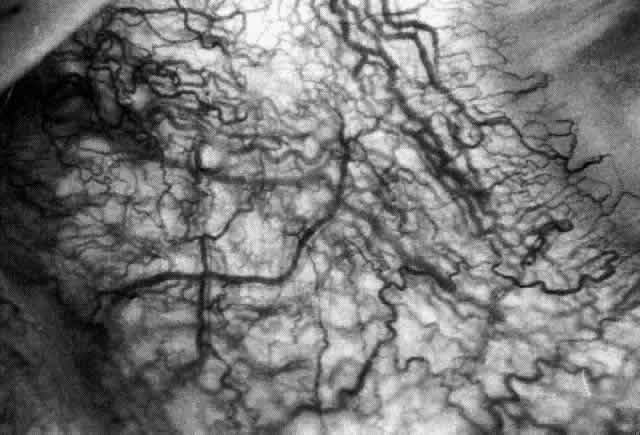

Diffuse Anterior Scleritis Diffuse anterior scleritis is the most common and least severe type of scleritis. The inflammation is widespread, and it may involve either a small segment or the whole of the anterior segment, sometimes with such severe overlying inflammation as to justify the name “brawny” scleritis (Fig. 29). On slit lamp examination, the vascular pattern of both deep and superficial layers may be distorted, so that the normal radial pattern of the vessels is lost; large anastomotic channels develop, leading to beading and tortuosity of the remaining vessels (Figs. 30 and 31; Color Plate 1C).

In this relatively benign form of scleral inflammation, the fluorescein angiogram reveals a rapid flow pattern in which the transit time of the dye is very rapid (as in episcleritis) (Figs. 32 and 33). Subtle changes occur in the capillary network, and abnormal leaking vessels appear after prolonged inflammation. These changes do not disappear after the inflammation subsides or is treated (see Fig. 31).